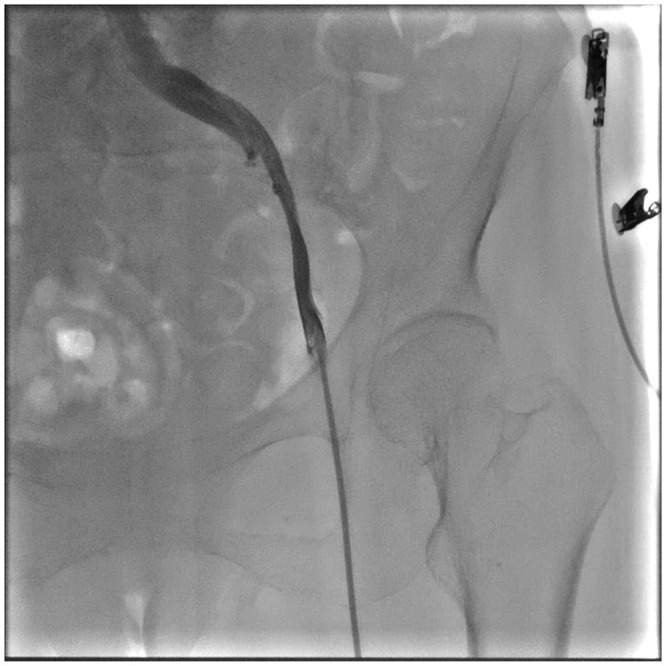

Case presentation: We report the case of a 74-year-old female with sick sinus syndrome, chronic kidney disease, type 2 diabetes, and severe bilateral iliac vein stenosis, who was deemed high-risk for conventional pacemaker implantation. After failed attempts through both femoral veins, the right internal jugular vein (RIJV) was successfully used as an alternative access route for Micra leadless pacemaker implantation. The procedure was performed under ultrasound and fluoroscopic guidance without complications. Post-procedure, the pacing threshold was 0.75 V, sensing was 8.5 mV, and impedance was 760 Ω, all within normal limits.